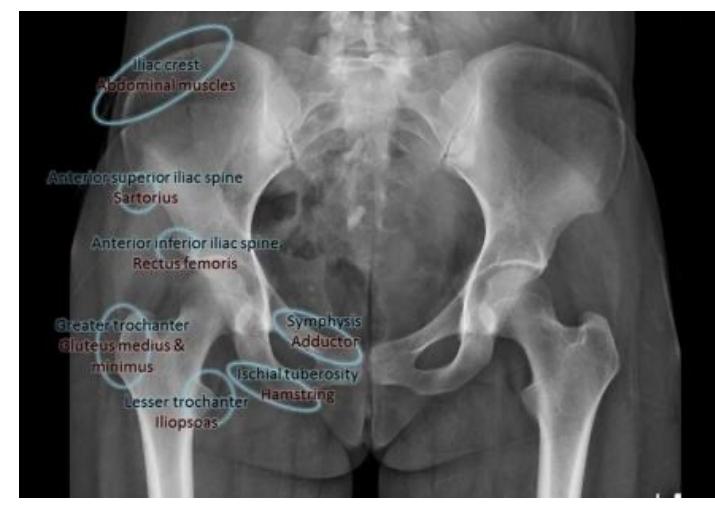

Pelvic Anatomy

Which of the following muscles is attached to the structure pointed by the arrow?

- C. Sartorius

Note: Arrow was pointing at ASIS (Anterior Superior Iliac Spine)

- A. Hamstring